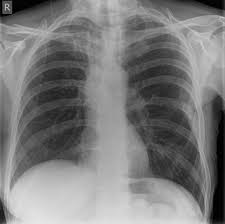

Signs Of Breast Cancer Recurrence In Lungs - P66shca Functions As A Contextual Promoter Of Breast Cancer Metastasis Breast Cancer Research Full Text - More generalized symptoms of cancer, such as fatigue and unintentional weight loss, may also signal a recurrence.. Breast cancer can come back as a local recurrence (in the treated breast or near the mastectomy scar) or as a distant recurrence somewhere else in the body.the most common sites of recurrence include the lymph nodes, the bones, liver, or lungs. When breast cancer moves into the lung, it often doesn't cause symptoms. It can also return and spread to other parts of the body (called metastasis or distant recurrence). Metastatic breast cancer after treatment for early or locally advanced breast cancer (stages i, ii and iii), it's possible for breast cancer to return (recur) and spread to other parts of the body (metastasize). Many of them share symptoms.

Local recurrence is usually found on a mammogram, during a physical exam by a health care provider or when you notice a change in or around the breast or underarm. Many of them share symptoms. Distant recurrence occurs when breast cancer returns in areas further away from the initial site, such as the bones, the lungs, or the brain. Metastatic breast cancer is cancer that's spread from the breasts. The most common sites for breast cancer to spread are the brain, lung, liver and/or.

These are the locations where the recurrence is most often diagnosed. If your breast cancer has metastasized to your lungs, you may not notice any symptoms right away. Symptoms and diagnosis when breast cancer moves into the lung, it often doesn't cause symptoms. If cancer cells are blocking the lymph nodes in. Cancer that comes back after treatment is called a recurrence.but some cancer survivors develop a new, unrelated cancer later. This is the most common type of breast cancer.it begins in. Each person's risk of breast cancer recurrence is different and depends on many factors, such as the size, type, grade and features of the cancer and whether the lymph nodes were affected. Pain or discomfort in the lung This recurrence is also known as metastatic recurrence and cancer travels to the far places in the body like bones, lungs and sometimes even to liver. Pain in your bones, which may get worse when lying down; Symptoms of metastatic breast cancer in the. It causes pain in the bone and chest, continuous dry cough, loss of appetite, nausea and vomiting with severe headaches and fever with chills. Distant recurrence a distant (metastatic) recurrence means the cancer has traveled to distant parts of the body, most commonly the bones, liver and lungs.

The symptoms of a local cancer recurrence are specific to the original cancer. Symptoms and diagnosis when breast cancer moves into the lung, it often doesn't cause symptoms. Download a quick guide to the signs and symptoms of secondary breast cancer. It can also return and spread to other parts of the body (called metastasis or distant recurrence). Breast cancer tends to metastasize preferentially to the bone, lung, liver, spine and larger bones, brain, in that order of prevalence.